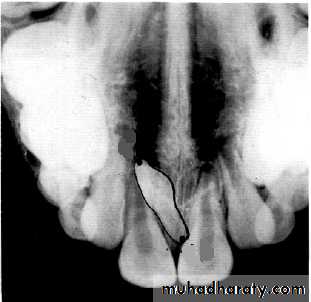

incisor film

canine filmIs the displaced incisor (arrows) located on the buccal or the lingual?

5

The lateral incisor is displaced to the lingual. The tube head moves distally from the incisor film to the canine film. The lateral incisor also moves distally, covering half the canine on the canine film.